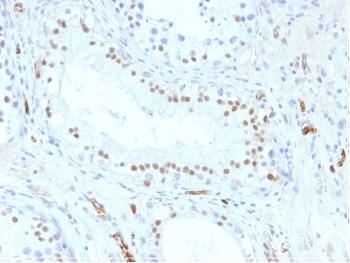

IHC testing of formalin-fixed, paraffin-embedded human testis stained with WT1 antibody (clone WT1/857). Required HIER: boil tissue sections in pH 9 10mM Tris with 1mM EDTA for 10-20 min followed by cooling at RT for 20 min.

IHC testing of FFPE human mesothelioma with WT1 antibody (clone WT1/857). Required HIER: boil tissue sections in pH 9 10mM Tris with 1mM EDTA for 10-20 min followed by cooling at RT for 20 min.

IHC testing of FFPE rat testis with WT1 antibody (clone WT1/857). Required HIER: boil tissue sections in pH 9 10mM Tris with 1mM EDTA for 10-20 min followed by cooling at RT for 20 min.

The antibody produces strong nuclear staining in mesothelial cells, renal podocytes, and hematopoietic tissues. In diagnostic pathology, WT1 detection is widely used in panels to distinguish mesothelioma from adenocarcinoma. It also supports evaluation of Wilms tumor and certain leukemias, providing pathologists with a reliable diagnostic tool.